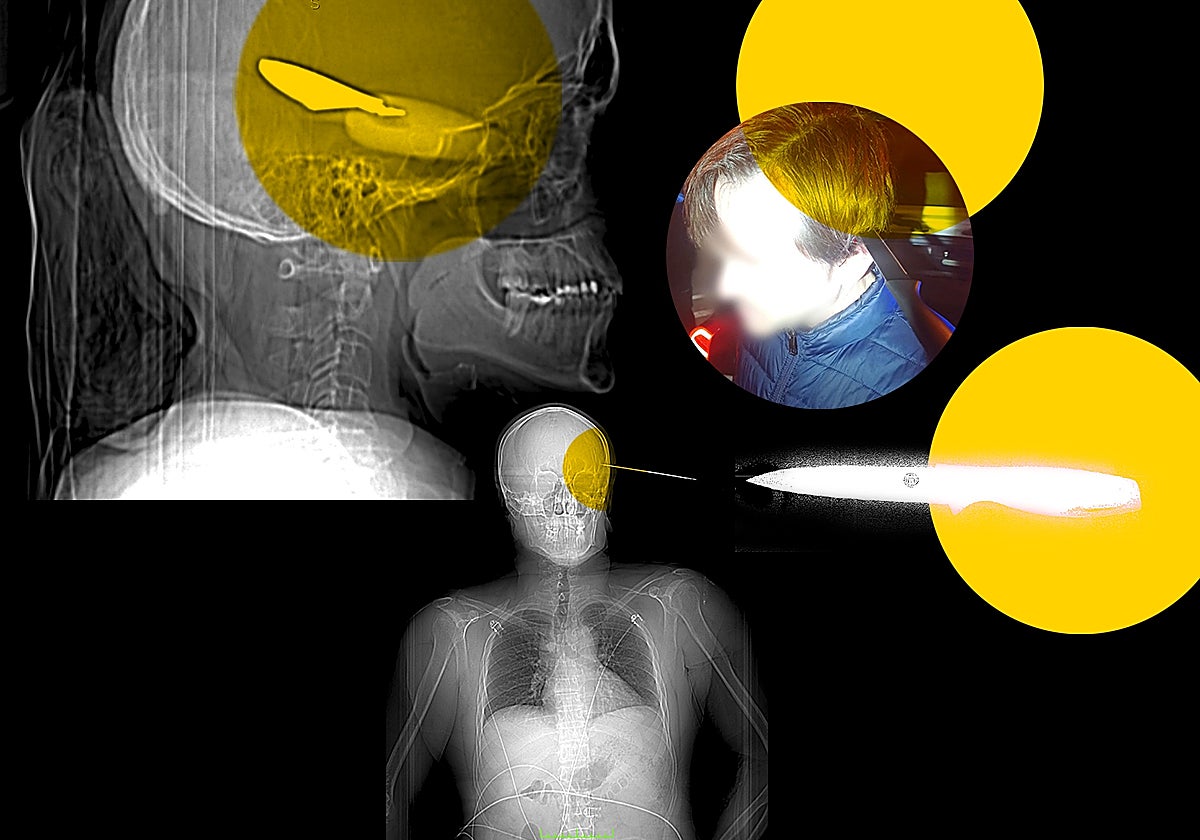

Antonio, el hombre que sobrevivió a un cuchillo incrustado en la cabeza: «Salió a cazar, iba a matarme»

Un menor de 16 años fue detenido en Mijas por apuñalarlo con tal violencia que le dejó el arma blanca clavada en el cráneo

Los agentes no daban crédito a lo que veían. Uno de ellos hasta le hizo una foto con el cuchillo incrustado en la cabeza. Cuesta creer que la imagen sea real. «Parece un disfraz de Halloween», le dijo el propio Antonio a un amigo que se resistía a verla por su dureza.

En urgencias del Hospital Regional lo atendieron dos neurólogos. Le hicieron un escáner y comprobaron que la hoja del cuchillo había llegado a atravesar el cráneo -de hecho, se quedó incrustada en él- y estaba rozando el cerebro. «Un milímetro más y los daños habrían sido irreversibles o me habría causado la muerte», confiesa el propio Antonio.

El equipo médico le anunció que debían operarlo de urgencia. Antonio despertó a la mañana siguiente en la unidad de cuidados intensivos (UCI) del hospital. «Me explicaron que me había fisurado el cráneo y que me habían tenido que poner una chapa a modo de parche. Durante la operación exploraron la zona que podía estar afectada y comprobaron que no había más lesiones ni un derrame interno», aclara.

El caso de Antonio es tan extraordinario que hasta está siendo estudiado por los profesionales del Instituto de Medicina Legal (IML) de Málaga. Por ahora, no tiene secuelas graves -son más psicológicas que físicas-, aunque el riesgo de infección aún no ha desaparecido del todo. Le colocaron 20 grapas en la cabeza, donde le queda una cicatriz que le recuerda cada día lo que pasó. Esto fue, según su versión, lo que ocurrió.